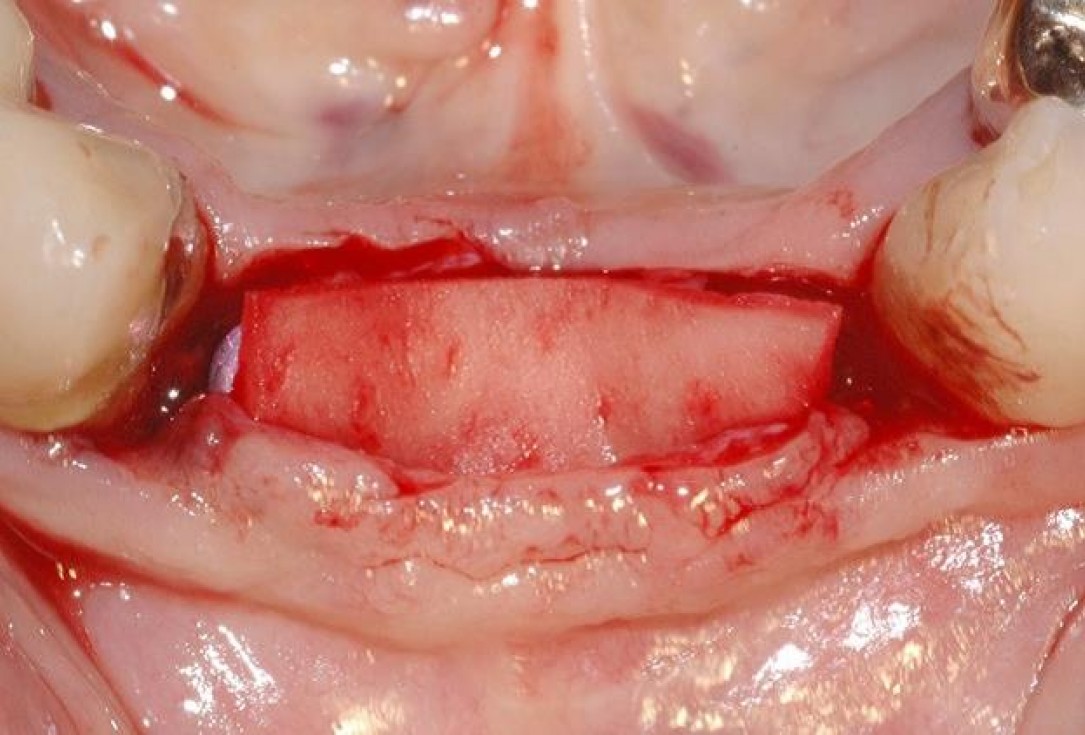

3/15 - Defect dimensions visible after full thickness flap preparationSoft tissue augmentation and GBR with mucoderm® and maxresorb® - Dr. S. Scherg